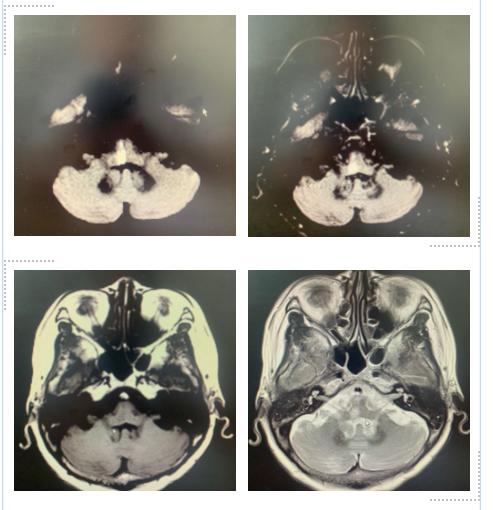

医院里,老朱经过核磁共振的检查后,得到了确诊,右侧延髓梗死。

老朱的延髓出现了梗死病灶,梗死灶造成球麻痹,直接表现出来的症状为吞咽困难,饮水呛咳,头晕等。